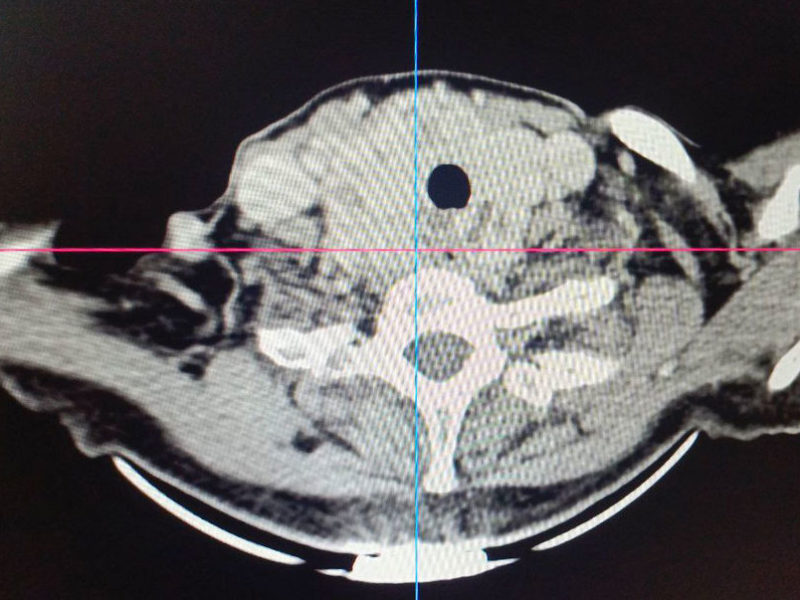

Операции предшествовало комплексное обследование, включавшее компьютерную и магнитно-резонансную томографию, в результате которых было принято решение о проведении срочного хирургического вмешательства. В настоящий момент состояние пациентки стабилизировалось, она чувствует себя хорошо выписана домой для дальнейшей реабилитации.